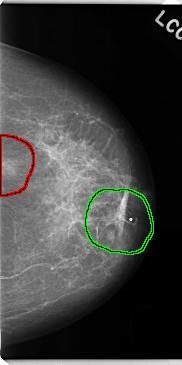

FILE: C_0146_1.LEFT_CC.OVERLAY

TOTAL_ABNORMALITIES 2

ABNORMALITY 1

LESION_TYPE MASS SHAPE OVAL MARGINS ILL_DEFINED

ASSESSMENT 4

SUBTLETY 4

PATHOLOGY MALIGNANT

TOTAL_OUTLINES 1

ABNORMALITY 2

LESION_TYPE MASS SHAPE IRREGULAR MARGINS ILL_DEFINED

ASSESSMENT 5

LEFT_CC LINES 4736 PIXELS_PER_LINE 2360 BITS_PER_PIXEL 12 RESOLUTION 50 OVERLAY